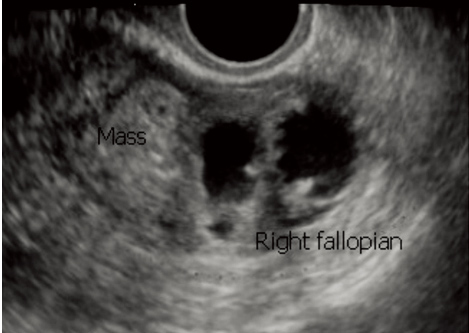

超声表现:子宫后位,宫体大小约4.9 cm×4.0 cm×4.2cm;宫内光点分布均匀,内膜居中,双层厚约:1.2 cm,双侧卵巢大小形态正常。右侧附件区探及迂曲囊状暗区,范围约4.9 cm×2.6 cm×4.2cm(图 1),形态规则,边界清晰,囊壁增厚,局部呈双边征,较厚处约0.4 cm,CDFI:囊壁上未见明显血流信号;其旁另见中等回声团块,范围约3.0 cm×2.6 cm(图 2),边界清晰,CDFI:内未见明显血流信号,两者紧贴,无法分离。盆腔内探及液性暗区,最大深度约1.7 cm。超声诊断:右侧输卵管积液合并扭转,盆腔少量积液。

| 图 1 右侧输卵管积水,彩色多普勒未显示血流信号 |

| 图 2 右侧输卵管积水旁中等回声团,彩色多普勒未显示血流信号 |